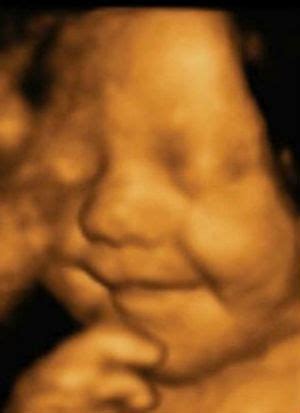

3D/4D echoskopija yra inovatyvus tyrimas, suteikiantis galimybę matyti ryškų vaisiaus ar kelių vaisių vaizdą trimatėje erdvėje. Skirtingai nei įprastas 2D ultragarsas, kuris pateikia plokščius, dvispalvius vaizdus, 3D echoskopija leidžia pamatyti vaisiaus veido bruožus, jo kūno formas ir struktūras realistiškiau. Aukščiausios klasės prietaisai, naudojami mūsų klinikose, suteikia galimybę stebėti, kaip mažylis žiovauja, čiulpia nykštį ar atlieka kitus judesius.

4D echoskopija žengia dar toliau, nes ji sujungia 3D vaizdus į trumpą filmuką. Tai reiškia, kad galima stebėti ne tik statinius vaisiaus atvaizdus, bet ir jo judesius realiu laiku - kaip jis spardosi, vartosi, mojuoja rankytėmis ar net bando apsiversti. Ši technologija leidžia išsamiai apžiūrėti vaisiaus veidą, rankas, kojas ir stebėti jo aktyvumą.